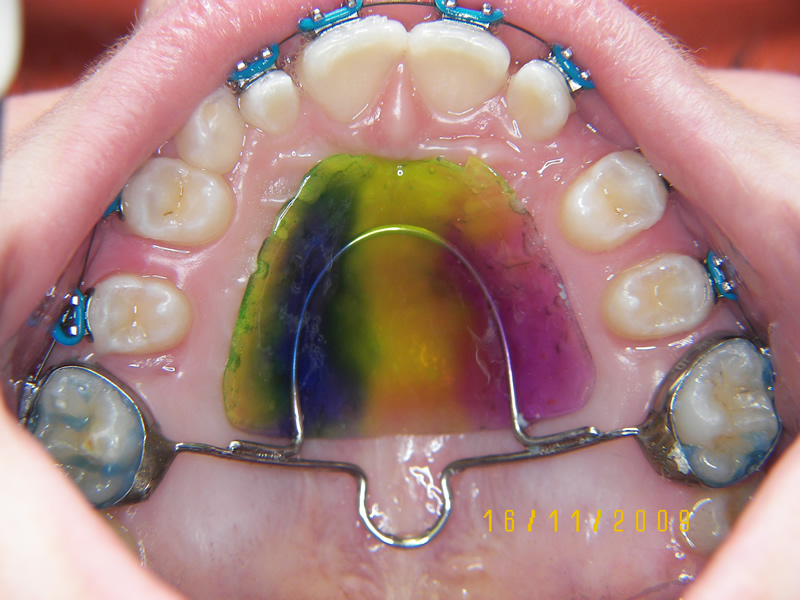

L'ortodonzia intercettiva include i trattamenti precoci (6-12 anni) con apparecchi mobili, funzionali, come attivatori, Frankel, Bionator, placche funzionalizzate e infinite altre.

Interveniamo sulla malocculusione in fase evolutiva, cercando di indirizzare la vettorialità di crescita, di ripristinare una normale funzionalità e modificare rapporti dentali anomali.

L'equilibrio armonico tra la muscolatura periorale e endorale ci porta ad ottenere risultati stabili nel tempo. In alcuni casi di malocclusioni gravi, sono gli stessi apparecchi "miofunzionali" che modificano o stimolano la funzione della muscolatura (terze classi, p.es. la postura linguale deve essere modificata per favorire la crescita del mascellare superiore).